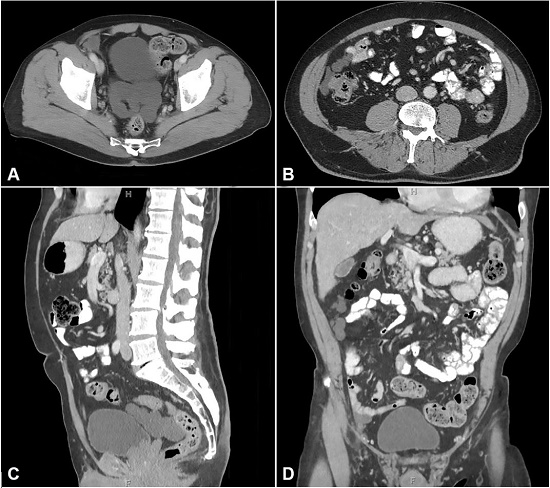

The patient is a 60-year-old male who initially presented to the emergency department with acute onset, throbbing, episodic right flank pain, associated with nausea and hematuria. There was a concern for renal colic, and non-contrast computerized tomography (CT) of the abdomen/pelvis demonstrated a 0.6 cm calculus in the right proximal ureter causing right obstructive uropathy. An incidental 7.9 x 9.6 cm multi-lobulated cystic mass located posterior to the urinary bladder was also discovered. His nephrolithiasis was treated, and follow-up CT of the abdomen/pelvis with intravenous contrast confirmed a persistent, lobular, fluid-attenuation mass within the recto-vesical space, and additional lobular cystic lesions within the right colonic gutter (Figure 1). Ultrasound done demonstrated multi-loculated anechoic complexes with thick septations.

Most of the cases of BMPM are diagnosed incidentally on imaging or during laparotomy for other indications. In others, the clinical presentation depends on tumor bulk and location, with large lesions causing abdominal pain, fullness, distention, intestinal obstruction, nausea, vomiting, weight loss, and/or changes in bowel habits.4,13 Abdominal tenderness, abdominal distention, and palpable abdominal or pelvic mass may be present on physical examination. BMPM typically arise from the pelvic peritoneum but can also develop on the serosal surfaces of ovary, uterus, bladder, rectum, cul-de-sac, lymph nodes, spleen, and liver.3,4 In women, BMPM is typically located along the peritoneal surfaces of the posterior cul-de-sac. In men, BMPM commonly develops along the peritoneal surface of the recto-vesicular pouch. Ultrasound or CT reveals multicystic masses. In our case, also the ultrasound demonstrated multi-loculated anechoic complexes with thick septations14 and CT revealed well-defined, low attenuating, cystic abdominopelvic masses with possible enhancement.15 Magnetic resonance imaging (MRI) shows hyperintense signals reflecting cystic fluid, with possible gadolinium enhancement of the septa.16 In all imaging modalities, mild free-fluid and minimal peritoneal thickening may be noted – a stark contrast to malignant peritoneal mesothelioma, which frequently presents with frank ascites and diffuse peritoneal thickening. Diagnosis is achieved through surgical sampling with immunohistopathologic studies. It has also been suggested that the biologic behavior of the condition is worse in patients with high levels of CA125.7